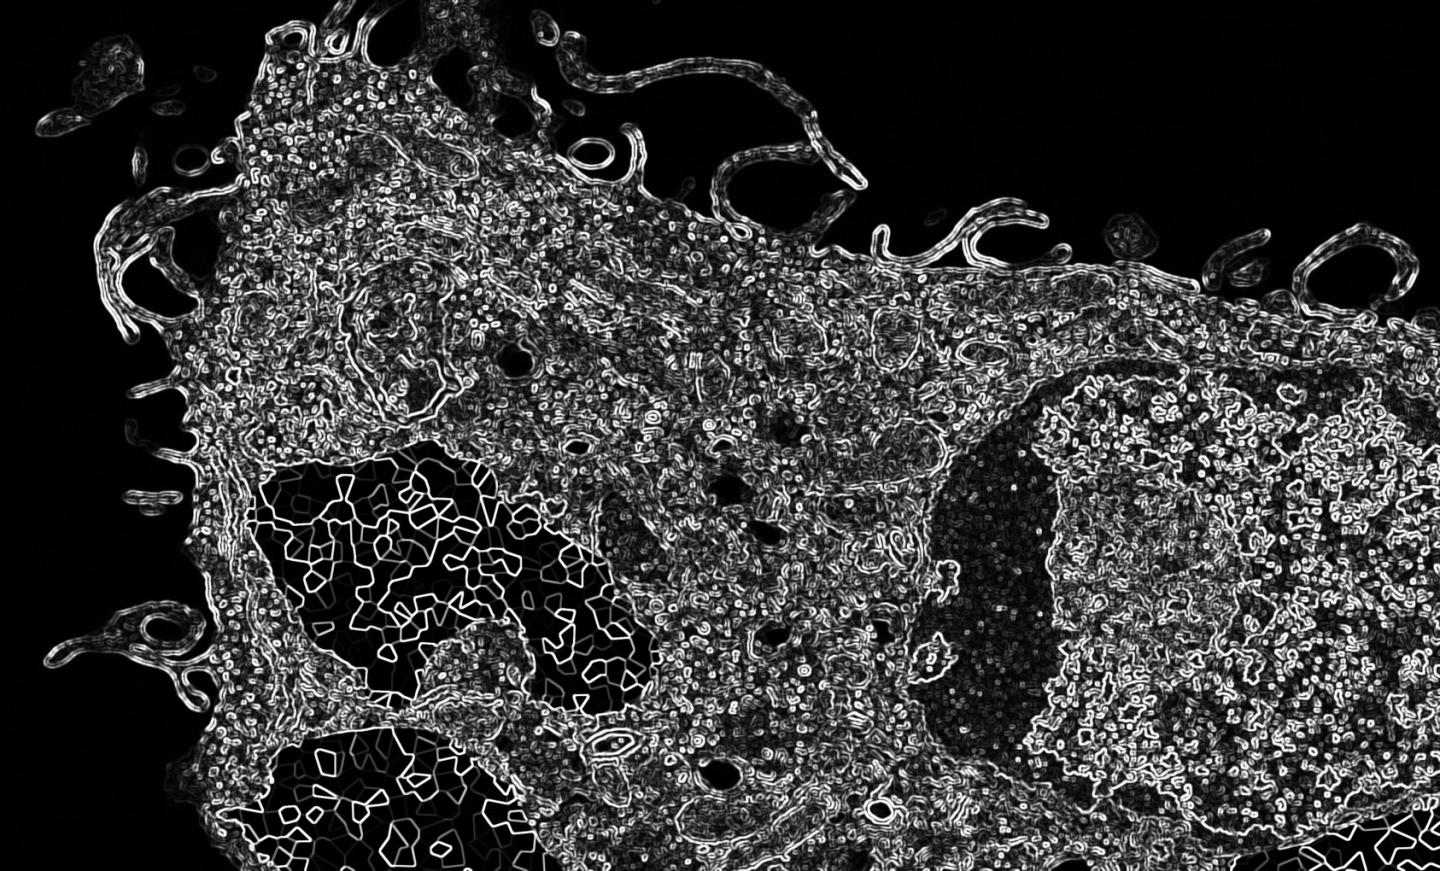

Hemozoin-Containing Macrophage

image: This is a hemozoin-containing macrophage, Hamza lab. view more

Credit: Hamza lab